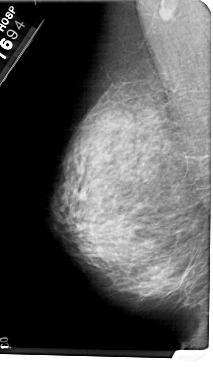

A_1985_1.LEFT_MLO

LEFT_MLO LINES 5491 PIXELS_PER_LINE 3181 BITS_PER_PIXEL 12 RESOLUTION 43.5 NON_OVERLAY